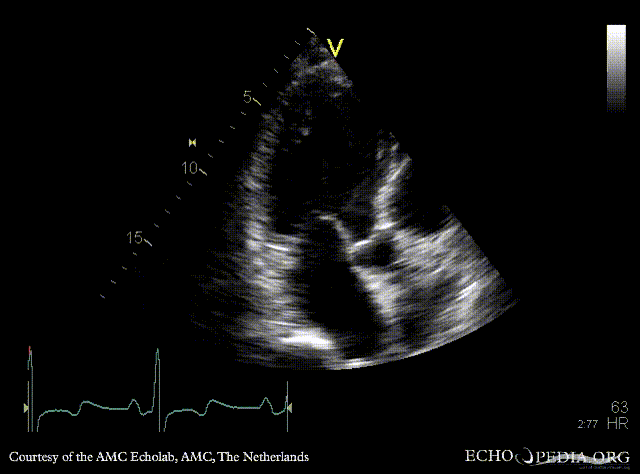

Case 159